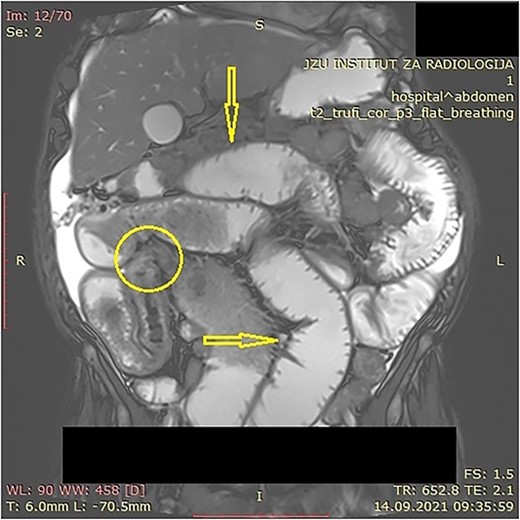

The patient was initially treated with monthly intramuscular doses of 20 mg of octreotide LAR (long-acting somatostatin analog) over a period of 5 months. During this period, the patient subsequently developed gradual partial small bowel obstruction, manifested with episodes of cramp abdominal pain and difficulties in bowel movement. Abdominal computerized tomography (CT) scan and MR imaging enterography were indicated. CT scan confirmed the presence of liver metastases and thickened small bowel wall with no confirmation of primary tumor existence (Fig. 1). MR enterography revealed small bowel distension with visible zone of transition in the right hemi abdomen (ileum) with restriction of diffusion (low signaling of apparent diffusion coefficient map) with surrounding desmoplastic reaction and visible irregular tumor with measured dimensions of 24 × 18 mm (Fig. 2).

Abdominal CT scan showing small bowel wall thickening described as chronic small bowel obstruction (arrow).

MR enterography with dilated small bowel loops (arrows) and visible zone of transition with visual tumor in the ileum (encircled).